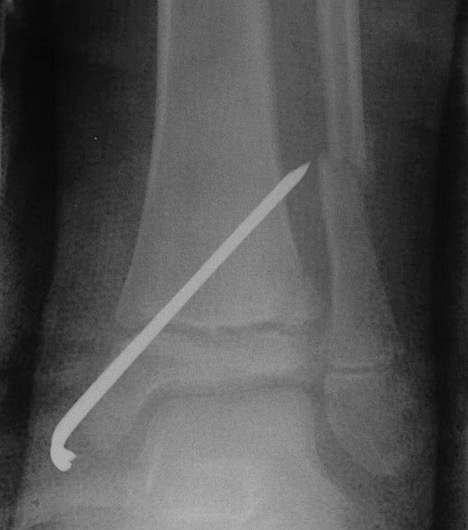

Management

ORIF

- > 2mm displacement

- usually anterolateral approach to reduce

- epiphyseal medial-lateral screw

- metaphyseal AP screw

Complications

Growth arrest 10%